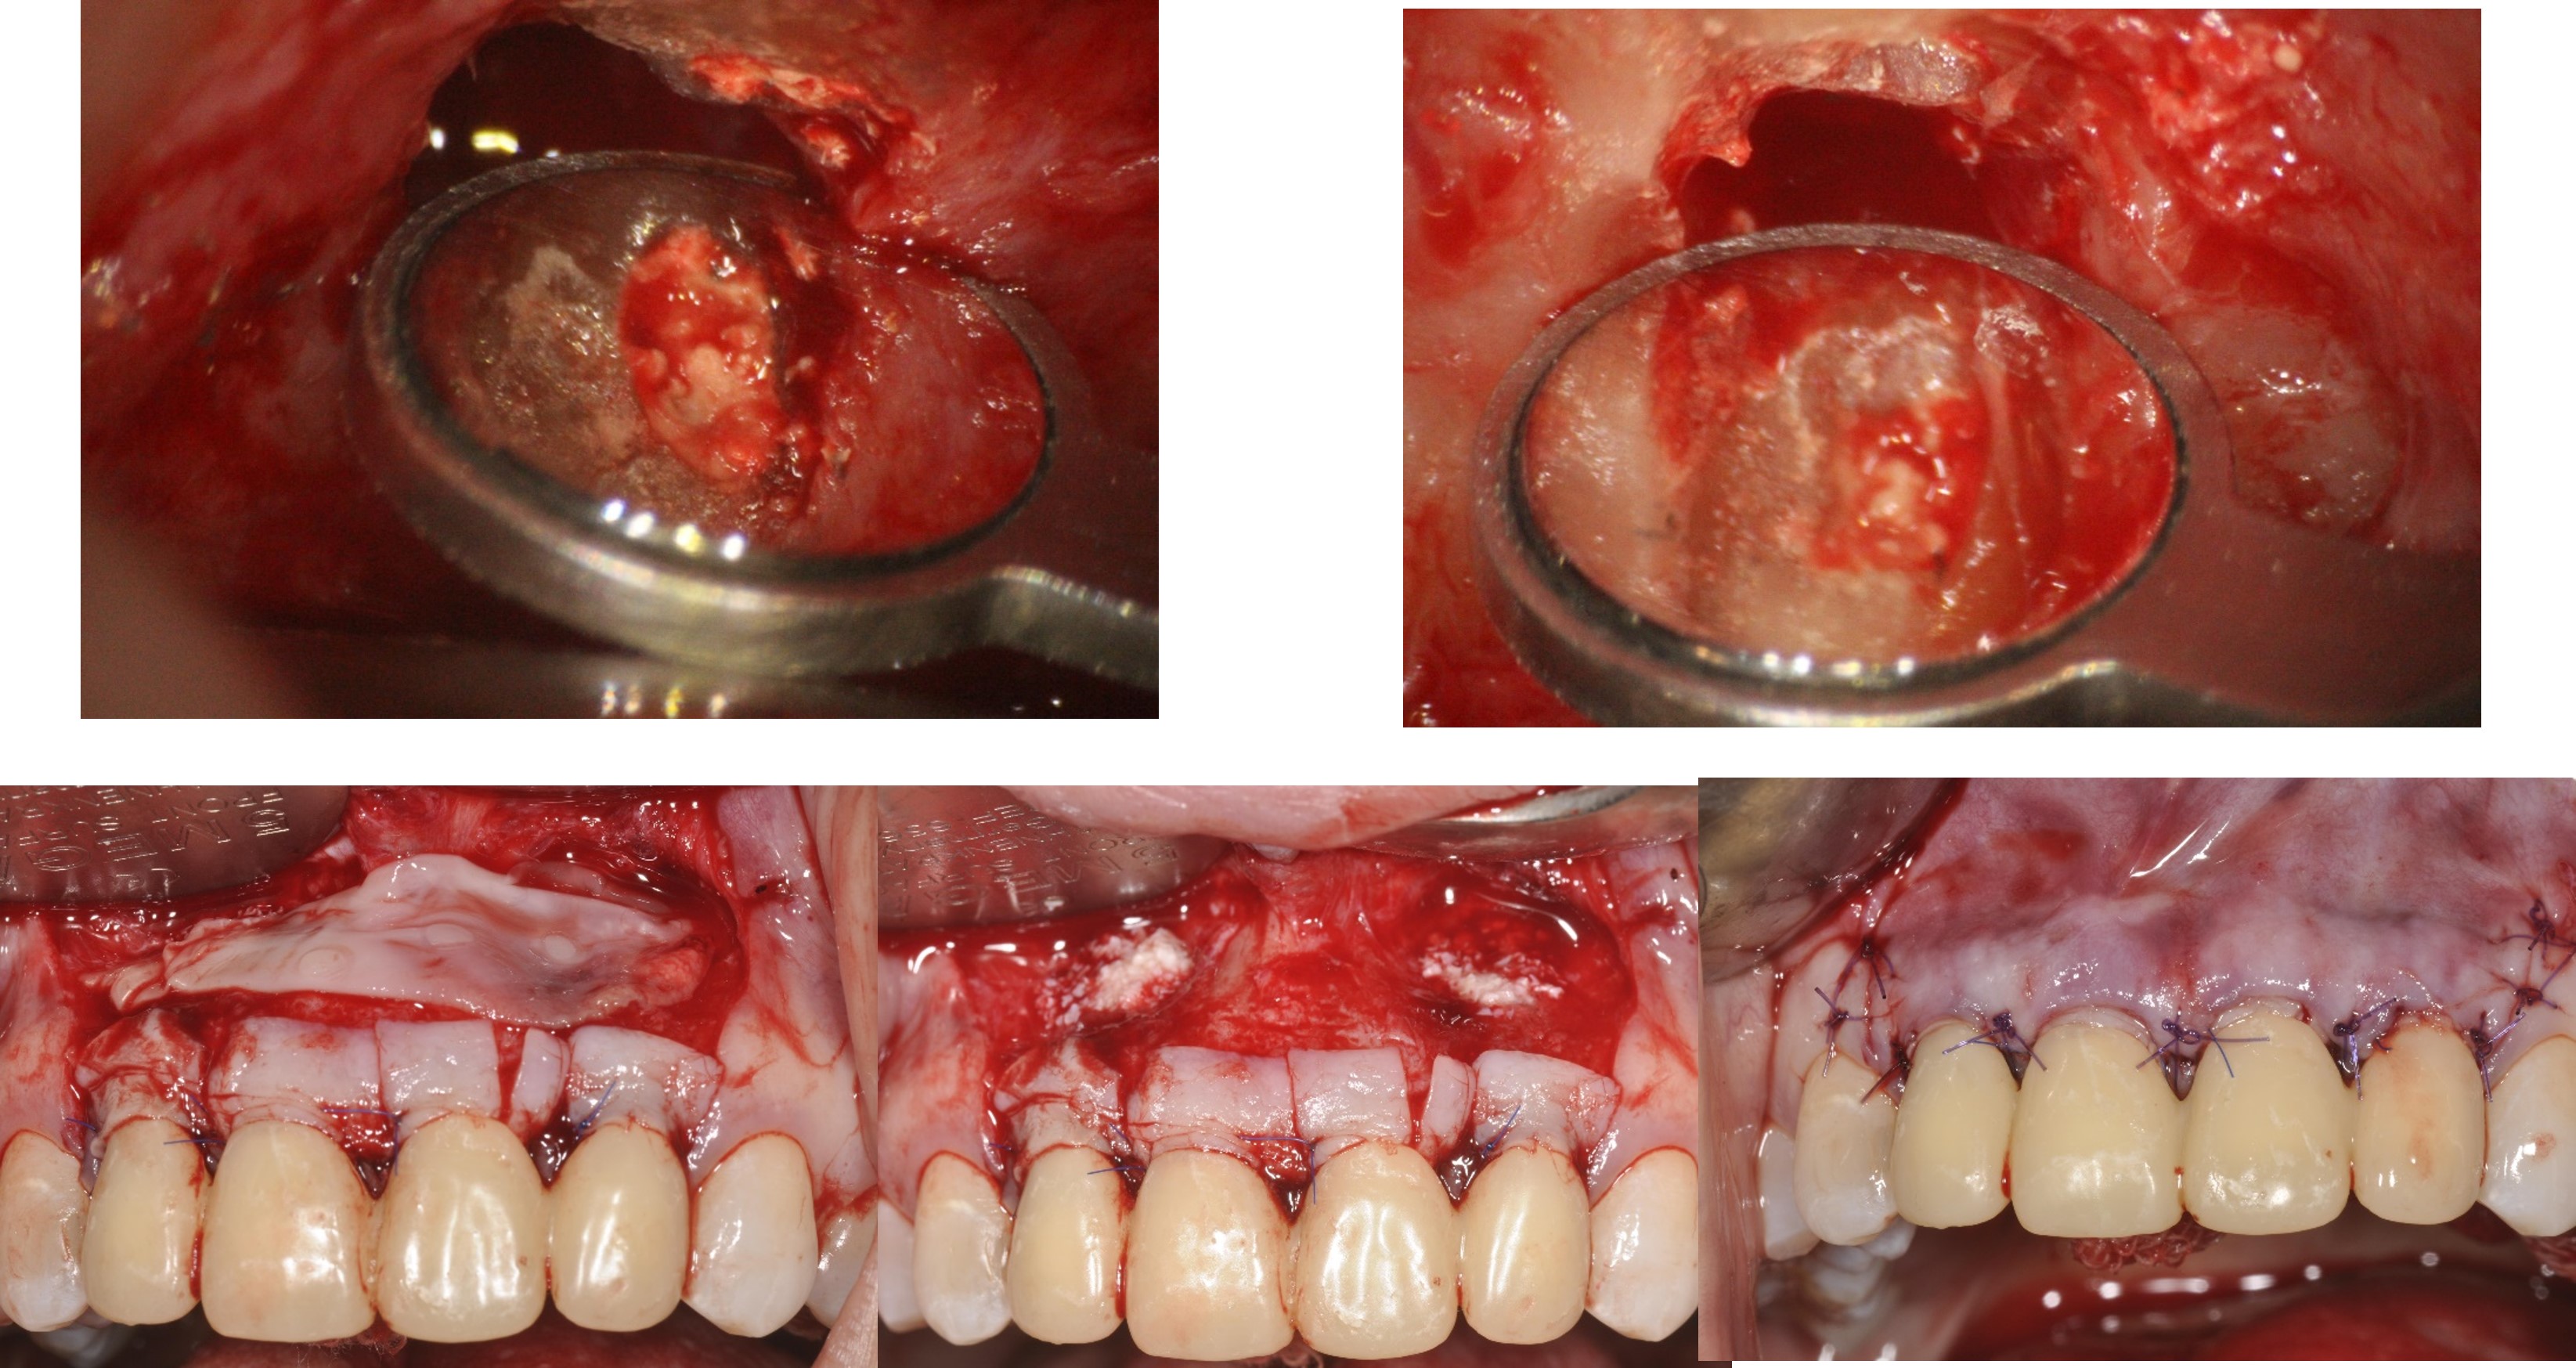

阻生齒拔除,骨膠原修復

前牙顯微根尖手術

軟組織恢復更理想